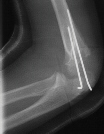

A five year and six month old white male sustained a fall

onto his outstretched right arm with immediate complaints of pain

and swelling in his right elbow. The child was unable to move

his arm secondary to pain. He was on the play ground and the fall

was not witnessed. Physical examination revealed swelling, tenderness

and crepitus over the lateral aspect of the elbow. The skin was

intact and neurovascular examination of the right upper extremity

was without deficits. The patient was taken to the operating room

where under general anesthesia and tourniquet control, the fracture

was exposed utilizing an anterolateral approach. Two diverging

k-wires were placed across the fracture site.